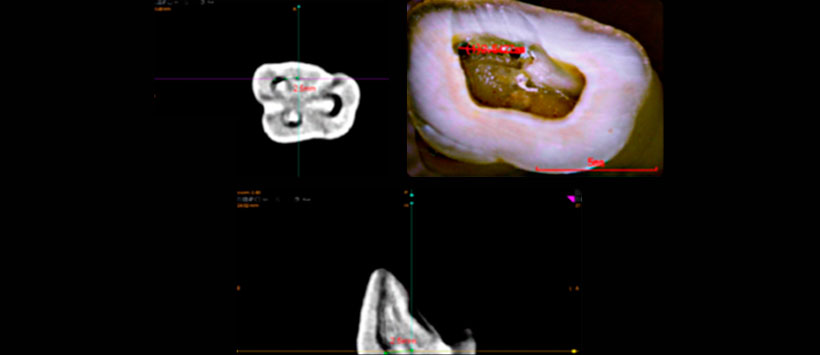

Los objetivos del presente estudio fueron: 1) determinar la incidencia de la configuración apical de los conductos MV1 y MV2 de primeros molares superiores teniendo en cuenta la clasificación II (2-1) y VI (2-2) de Vertucci (Figura 1 Y Figura2); 2) obtener la distancia media entre los orificios MV1 y MV2 a la altura del piso de la cámara pulpar; y c) analizar la relación entre la distancia interorificio y la configuración apical de la raíz MV de primeros molares superiores, en una muestra de población de Colombia.

Por lo cual se analizó un total de 113 imágenes tomográficas computarizadas de la zona de molares superiores. El análisis consistió en medir la distancia entre los orificios de la raíz MV del primer molar superior a la altura del piso de la cámara pulpar para determinar si hay correlación con el tipo de configuración apical de la raíz MV.

Obteniendo como resultado la incidencia de configuraciones apicales II y IV fue del 41,59 % y 58,40 %, respectivamente. La distancia media entre los orificios de entrada de la raíz MV del primer molar superior para configuraciones apicales II y IV (clasificación Vertucci) fue 2,44 mm y 2,52 mm, respectivamente.

La configuración anatómica más común fue la tipo IV de Vertucci (58,40 % de los casos). La distancia media interorificio en el grupo estudiado fue de 2,49 mm. No se encontró una relación entre la distancia interorificio y el tipo de configuración apical.